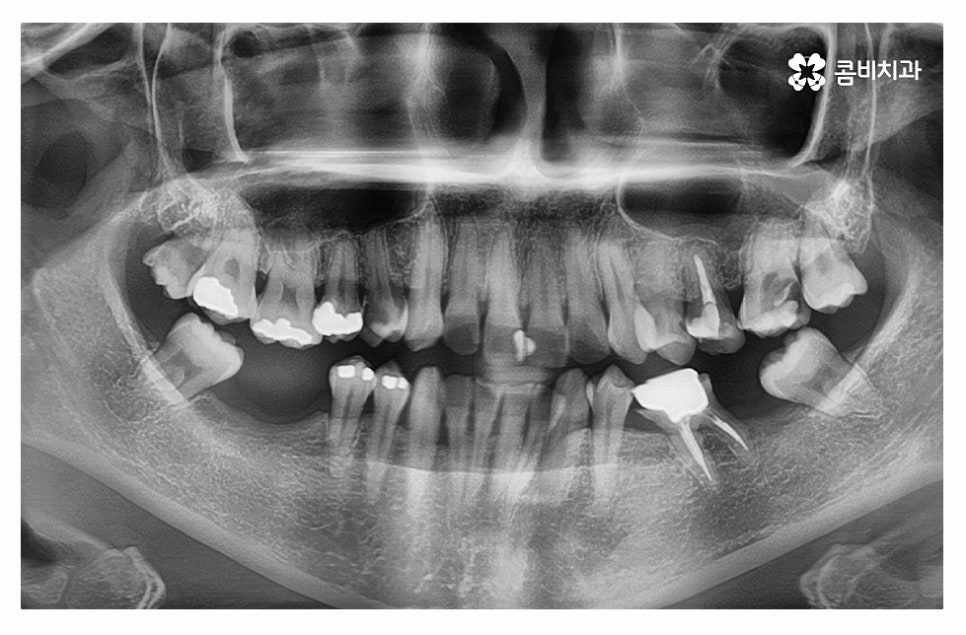

오늘 보시는 환자분의 경우에는 치주질환이 심해져서

여러 치아를 발치하게 된 사례로 자연치아의

수명을 다하지 못한 채 발치를 하는 것은 안타까운 일이지만

치주질환 관리를 제대로 하지 못할 경우에는

노년에 이르러 치아를 모두 상실하게 되는 경우도

많기 때문에 중년 이후에는 특히 주의할 필요가 있어요.

위 이미지에서 보시는 것처럼 치주염으로 인하여

잇몸뼈가 많이 내려간 경우 음식물이 잘 끼고 관리가 잘 안되면서

치아가 깊게 뿌리내리지 못해 흔들리게 되고

치아가 제대로 된 기능을 하지 못하여 발치까지 진행되는 경우가 있는데

위 환자분도 사랑니가 이런 경우에 해당되어 발치를 진행한 사례라고 할 수 있어요.